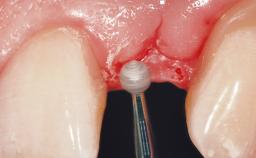

Immediate Flapless Placement of an Implant in a Maxillary Right Lateral Incisor Site

This 43-year-old male patient, a non-smoker, came to our practice because of a fracture of tooth 12 caused by a bicycle accident. Due to the combined para- and infrabony crown and root fracture, tooth extraction, and subsequent implant placement were suggested to the patient as the therapy of choice. The patient had high esthetic expectations with regard to the treatment outcome and asked for an immediate fixed provisional restoration. His individual esthetic risk profile summed up to a medium esthetic risk.

Loading Protocol Immediate

Provisional Implant-Supported Prosthesis Prosthodontic margin > 3 mm apical to mucosal margin Prosthodontic margin > 3 mm apical to mucosal margin